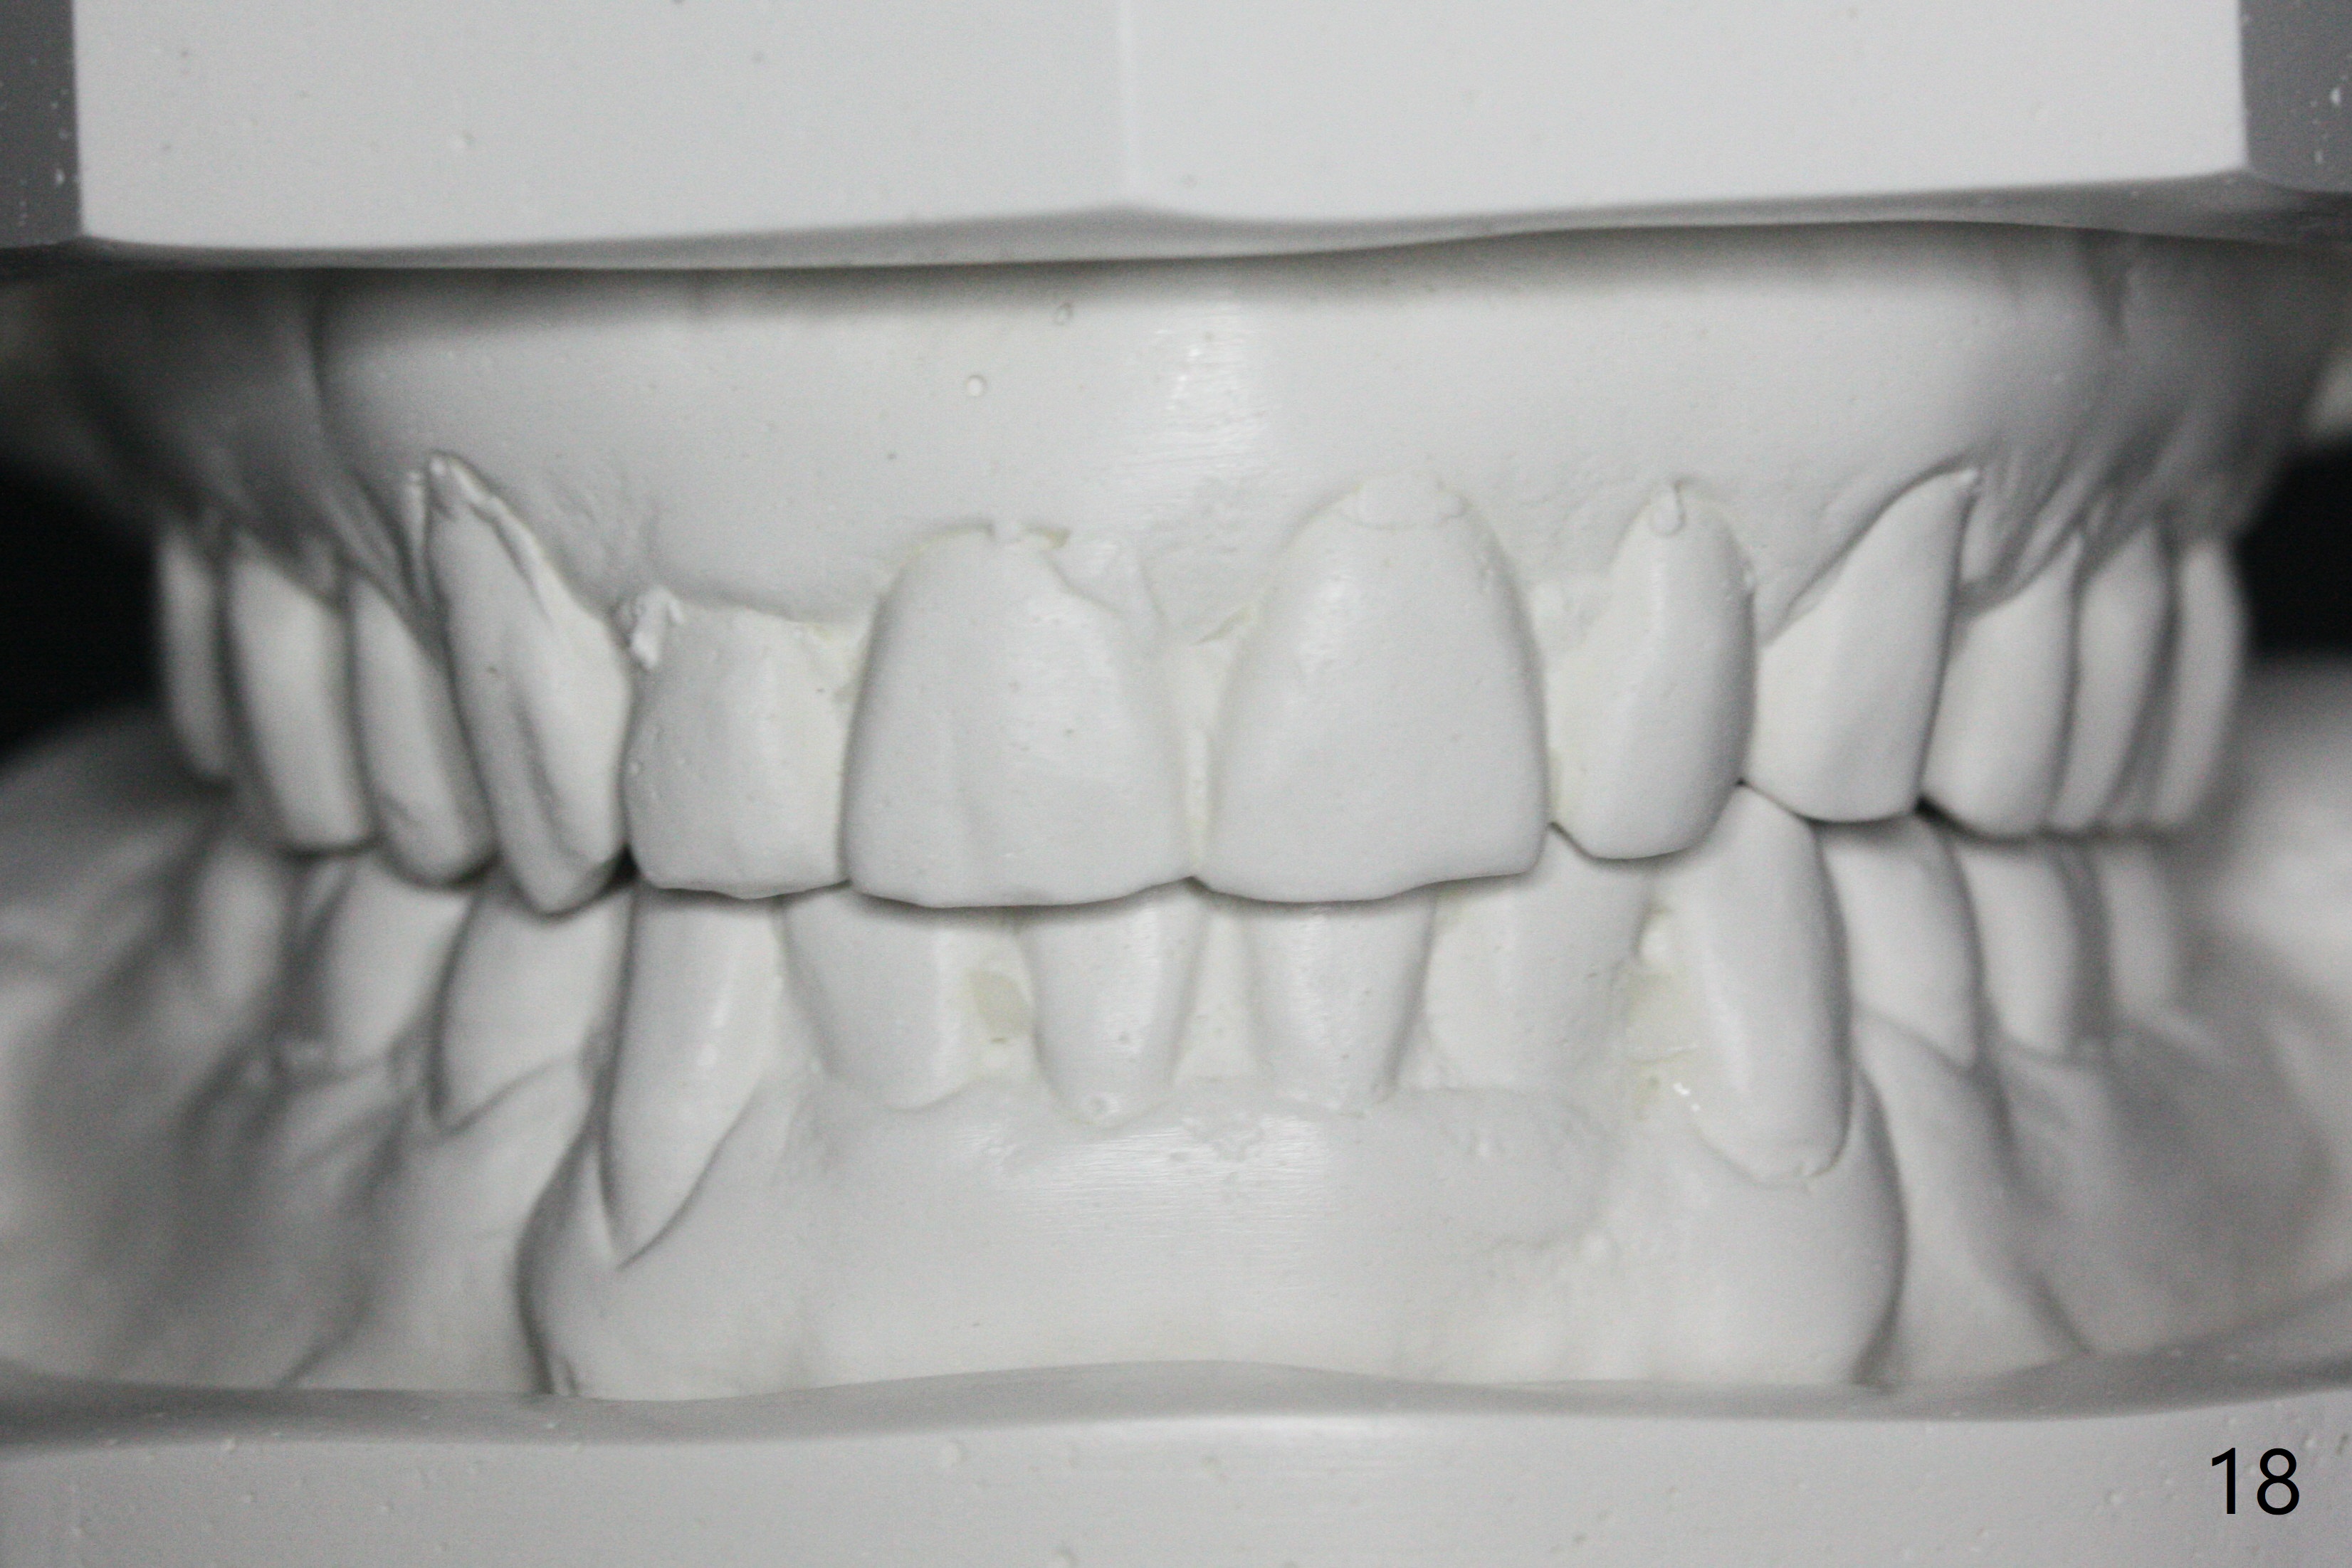

Enough Space For Crowding After Extraction? A 47-year-old man requests orthodontic treatment following SRP in other office (Fig.1-11). For severe crowding and midline shifting, extraction of four of the 1st bicuspids is imminent. Is it enough? To answer the question, model surgery is performed (Fig.12-16). 1st visit: periodontal maintenance, orthodontic consent (emphasizing oral hygiene) extract 4s and possibly L8s and separators. The beauty of this vist is that after local anesthesia and extraction including L8s, it is painless and easy to remove calculus from the proximal surfaces of the neighboring teeth. It is much easier to place separators after extraction. It is expected that there is no gingival erythema when the patient returns for bracketing. Take photos of UR3, similar to Fig.3. Molar banding is also anticipated to be easy with separator placement after extraction. Return to Ortho Cases Xin Wei, DDS, PhD, MS 1st edition 11/23/2017, last revision 04/28/2019